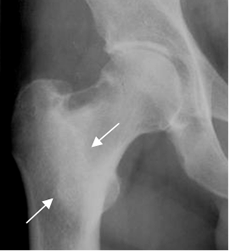

Fig 64. Osteoblastoma.

Mayor frecuencia entre la 2º y 3º décadas. Predominio en columna, sacro y huesos largos. Lesión metafisodiafisiaria y en los elementos posteriores de las vértebras, de ubicación cortical.

Fig 65. Osteoblastoma.

Rx AP. Lesión densa en la región intertrocantérica, por osteoblastoma.